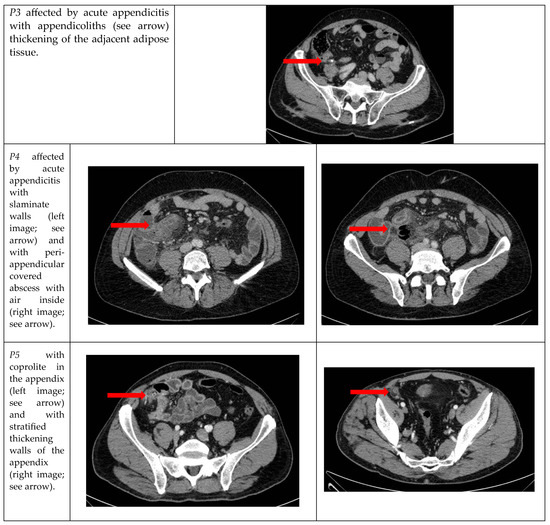

| P3 | M | 79 years | 27.5 | WBC 12.23 109/L, CRP 1.79 mg/dL | Atrial fibrillation in treatment with new oral anticoagulant; high blood pressure | Caucasian |

| P4 | M | 52 years | 26.8 | WBC 22.37 109/L, CRP 17.19 mg/dL | No | Caucasian |

| P5 | M | 65 years | 27.9 | WBC 18.06 109/L, CRP 7.48 mg/dL | No | Caucasian |